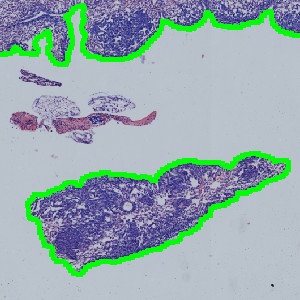

Result of analysis with APP: “01 Tissue Detect”. The lung tissue is automatically outlined.

APP: “01 Tissue Detect”

This APP can be used for automatic and precise identification of tissue present on image.

Step 1: Load the APP for tissue detection “01 Tissue Detect” which outlines the lung tissue in the image.

The first image processing step involves a segmentation of the lung tissue (see FIGURE 1). Afterwards the metastases are identified together with the regions that are either too misshaped, too red or too sparse for being identified as metastases (see FIGURE 5). The parameters defining the shape and sparseness of the metastases can easily be adjusted by the user.